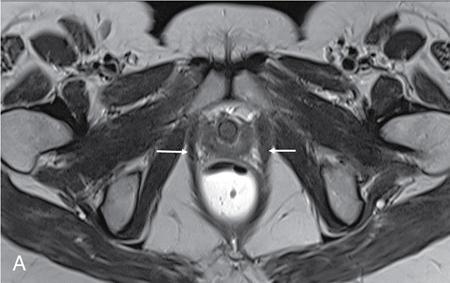

PELVIC FLOOR IMAGING – ANTERIOR AND MIDDLE COMPARTMENTS Anu Epean, Deepa Korula The term ‘Pelvic floor disorder’ refers to dysfunction of the pelvic floor musculature and connective tissues which provide support for the pelvic organs. This can produce a wide range of symptoms such a urinary incontinence, straining to void, dyspareunia, constipation, faecal incontinence and organ prolapse. The greatest risk factors for pelvic floor disorders are female sex and advanced age. Other risk factors include obesity, pregnancy, multiparity, smoking, connective tissue disorders. The pelvic floor is broadly divided into three compartments. The bladder and urethra form the anterior compartment. The vagina and uterus form the middle compartment and the posterior compartment comprises of the rectum and anal canal (Fig. 7.16.1.1). The attachment of the fascia, muscles and the ligaments to the bony pelvis form the support for these structures. From cranial to caudal, there are three layers which make up the pelvic floor – the endopelvic fascia, the pelvic diaphragm and urogenital diaphragm. This is the most cranial layer of pelvic floor, lying deep to peritoneum. It is a fine structure, comprising of a network of connective tissue which encases the pelvic viscera, provides support to the pelvic organs and maintains their anatomic relationship. There are several condensations of this fascia and ligaments which provide support in each of the pelvic compartments. In the anterior compartment, a fascial condensation called pubocervical fascia extends from anterior vaginal wall to the pubis. Tear in the pubocervical fascia can cause cystocele and urinary incontinence. There are three groups of ligaments which provide urethral support – periurethral, paraurethral and pubourethral ligaments. The periurethral ligaments arise from medial fibres of pubococcygeus and pass ventral to urethra. The paraurethral ligaments connect the lateral wall of urethra to periurethral ligament and pubourethral ligament connects the lateral wall of urethra to arcus tendineus. The urethra lies on a Hammock-like supportive layer of endopelvic fascia and anterior vaginal wall, which are stabilized by attachment laterally to arcus tendineus and levator ani (Fig. 7.16.1.2). In the middle compartment, condensations of the endopelvic fascia which attach the uterus to the lateral pelvic wall is called parametrium, which is made up of the uterosacral and cardinal ligaments. The uterosacral cardinal ligament complex supports and suspends the cervix and upper vagina above the levator plate. More inferiorly, the paracolpium attaches the vagina to the lateral pelvic wall. There are three levels of fascial support to the vagina: In the posterior compartment, the perineal body located within the rectovaginal septum supports ligaments and muscles and prevents abnormal widening of levator hiatus (Fig. 7.16.1.3). The rectovaginal fascia extends from posterior wall of vagina to anterior rectal wall. A tear in the rectovaginal fascia is the cause for an anterior rectocele. Arcus tendineus levator ani (ATLA) is formed by the condensation of the endopelvic fascia laterally, along the pelvic sidewall. This extends obliquely from inferior pubic symphysis to ischial spine and provides lateral support to the pelvic organs and attachment of the levator ani. Fascial condensations are not visualized on imaging; however, organ prolapse, due to deficiency in any of these, can be detected on MRI. The levator ani and the coccygeus muscles make up the pelvic diaphragm. The levator ani is the primary muscle of the pelvic diaphragm and is attached to the pubis and to the ATLA laterally on both sides. The slow twitch fibres of the levator ani continuously contract, maintaining tone to the pelvic floor and suspending the pelvic organs in the correct position. The two most important components of the levator ani are the iliococcygeus and puborectalis muscles. The iliococcygeus arises from external anal sphincter and has a curved shape, concave inferiorly. It fans out laterally to its insertion in the posterior part of arcus tendineus (Fig. 7.16.1.4A and B). Posteriorly, in the midline, condensations of ilococcygeus form a firm raphe anterior to coccyx called the anococcygeal ligament or levator plate. The pubococcygeus muscle is a component of the levator ani. It forms the anteromedial part and is a thick bundle of fibres arising from the pubis and anterior portion of arcus tendineus. It extends horizontally back to behind the rectum, medially forming the margin of urogenital hiatus (Fig. 7.16.1.5A). The anorectal and urogenital hiatus are closed by the contraction of the pubococcygeus muscle. This enables support during rest and in situations where the intraabdominal pressure is increased. The medial fibres of pubococcygeus, depending on their attachment to urethra, vagina, anus and rectum are termed as pubourethralis, pubovaginalis, puboanalis and puborectalis, collectively as pubovisceralis. The puborectalis forms a sling around the rectum (Fig. 7.16.1.5B). The muscles of the pelvic diaphragm are well delineated on MRI. The urogenital diaphragm or perineal membrane is the most caudal layer of the pelvic floor. It has a triangular appearance, extending from the pubic symphysis and the ischiopubic ramus to the posterior perineal body. It is ventral to the external anal sphincter and perineal body. It is attached to the surrounding structures such as the perineal body, external anal sphincter, vagina and the bulbocavernosus muscle. Imaging has an increasing role in the evaluation of pelvic floor disorders. Clinical examination alone has a low sensitivity and specificity for the detection of multicompartment involvement and organ prolapse. Imaging helps to detect involvement of multiple pelvic compartments and thus to plan surgery. Ultrasound, MRI and conventional imaging which includes voiding cystourethrography, evacuation proctography and dynamic cystocolpoproctography (DCP) are used to evaluate the pelvic floor. It is easily available, cheap and does not involve ionizing radiation. In the evaluation of the anterior compartment, ultrasound is more reliable than MRI. Transperineal ultrasound using 2D, 3D or 4D techniques along with dynamic imaging helps to evaluate pelvic floor dysfunction. Patient is placed in a dorsal lithotomy position for a transperineal scan although a standing position can also be used. Convex transducer (2–6 MHz) or endoluminal transducers (endovaginal/endorectal) maybe used. In a midsagittal translabial scan, the anatomic relationship of urethra, bladder, vagina, cervix and anorectum can be studied and the relative position of these organs determined by use of certain measurements. The bladder-symphysis distance (BND) is the distance between the bladder neck and lowest margin of symphysis pubis and demarcates position of the bladder neck. Measurement of BND is made at rest and during Valsalva manoeuvre and the difference in BND between the two, gives the measure of bladder neck descent. There are no definite values to indicate normal descent but there is a proposed cut off of 20, 25, 30 mm to indicate hypermobility (Fig. 7.16.1.6A and B). The proximal urethra rotates posteroinferiorly during Valsalva manoeuvre and this can be measured by the posterior urethrovesical angle (β) or the gamma angle. The posterior urethrovesical or retrovesical angle (β) is the angle between a line through the urethral axis and the line through the trigonal surface of the bladder and varies from 90–120 degrees normally. This may increase to 160–180 degrees and can be associated with funnelling of bladder neck. The gamma angle is the angle between a line through the inferior margin of pubic symphysis and the urethrovesical junction. This is seen on Valsalva manoeuvre or at rest in patients with stress incontinence (Fig. 7.16.1.7). Color Doppler can demonstrate urine leakage on performance of Valsalva or at rest. Other abnormalities that can be detected on transperineal ultrasound are cystocele, urethral diverticulum, Gartner duct cyst, foreign body or bladder tumour. 3D pelvic ultrasound is useful to evaluate pelvic floor dysfunction and to study the urethra, levator ani complex, paravaginal supports, prolapse and implant imaging. 4D ultrasound helps in real-time, dynamic imaging of pelvic floor. In the middle compartment, although uterine prolapse is often clinically evident, it can also be detected by ultrasound. Uterine prolapse can be also quantified by measuring maximum descent of uterus from the reference point which is the inferior margin of pubic symphysis. Ultrasound is also useful to evaluate for surgical planning in a large retroverted uterus with an anteriorly placed cervix causing voiding symptoms. MRI is useful in the evaluation of pelvic floor as it provides good anatomic detail about the pelvic floor muscles, ligaments because of its inherent superior soft tissue resolution. In addition, dynamic MRI yields functional information. MRI defecography is a dynamic study performed to study the posterior pelvic compartment but it also gives information about the anterior and middle compartments. It can be performed both with closed magnet and open magnet systems. The patient is positioned supine with phased array coil around pelvis in a closed magnet system. In an open magnet system, the patient is in a sitting and more physiological position; however, due to the lower signal to noise ratio and lower resolution, a closed magnet system is preferred. Bowel preparation with use of laxative on night before the scan is optional. Voiding prior to the study is encouraged since an overdistended bladder can cause misinterpretation of results. Presence of some urine in the bladder is however, helpful to detect anterior vaginal prolapse. Instructions are given to the patient, prior to the procedure, about the ‘rest’, ‘squeeze’, ‘strain’ and ‘defecate’ phases of dynamic imaging, to ensure that movement or lifting of the pelvis does not occur during these manoeuvres. The rectum is filled with up to 200 mL of ultrasound gel. The patient is made to wear an adult diaper and covered with an incontinence pad on the gantry. Vaginal gel, ∼50 mL maybe introduced since this helps to delineate anatomic landmarks and detect uterovaginal prolapse. Initial large FOV T1 localizer scans help to identify the midline sagittal section of pelvis. T2-weighted fast spin echo, high-resolution sequences in sagittal, axial, coronal planes are used to obtain anatomic detail. This is followed by dynamic imaging of the pelvic floor with use of steady state imaging sequences such as True fast imaging with steady state precession (TrueFISP Siemens) and balanced fast field echo (balanced FFE Philips). Steady state sequences have the advantage of short acquisition times and higher signal to noise ratio and hence useful to obtain rapid serial midsagittal images while patient performs ‘squeeze’, ‘strain’ and ‘defecates’. There are several points and lines for measuring and staging pelvic organ prolapse on MRI; however, the PCL line is said to have the highest interobserver and intraobserver reliability of MRI measurements compared to all proposed reference lines and is described below: Pubococcygeal line (PCL): defined as the line that connects the inferior portion of the pubic symphysis to the last coccygeal joint. The PCL is the most commonly used reference line for the assessment of pelvic floor disorders (Fig. 7.16.1.8).